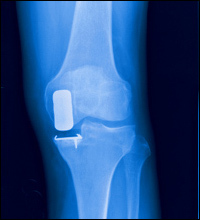

Uni-compartmental knee replacement surgery utilizes specially designed implants made to resurface one side of the knee joint, and eliminate activity-limiting arthritic pain restoring more normal knee function. They are attached to the ends of the femur (thigh bone) and tibia (shin bone), and move on one another during motion.

We remove the worn out and damaged cartilage surfaces of the shin bone (tibia) and thigh bone (femur) at the knee joint, including small segments of bone necessary for anchoring the implants. Surgical instruments are used to remove the proper amount of bone from the tibia and femur and to assure the correct alignment of the artificial implants.

The tibial and femoral implants are inserted covering the areas where the arthritic bone has been removed. These components will be secured to the ends of the bones with a caulk-like material known as bone cement.